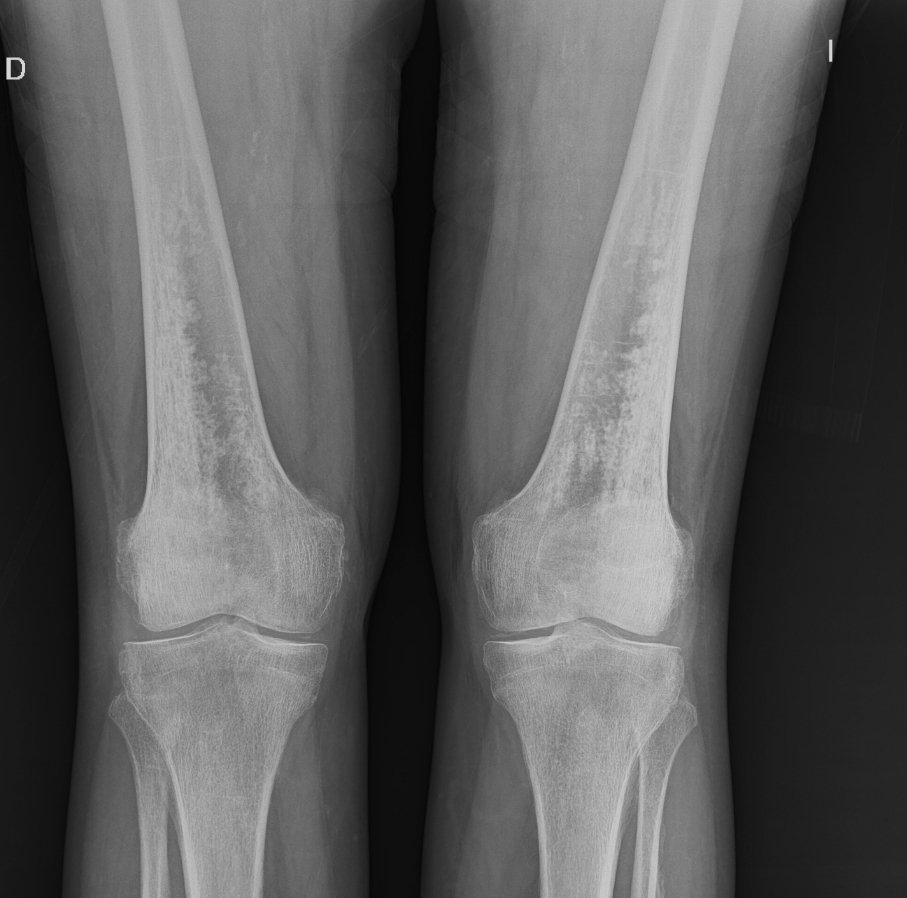

Histologically proven grade I cortical Chondrosarcoma.

#radres#foamrad#mskrad#Radiología#radiologypic.twitter.com/DOcITcDaQP